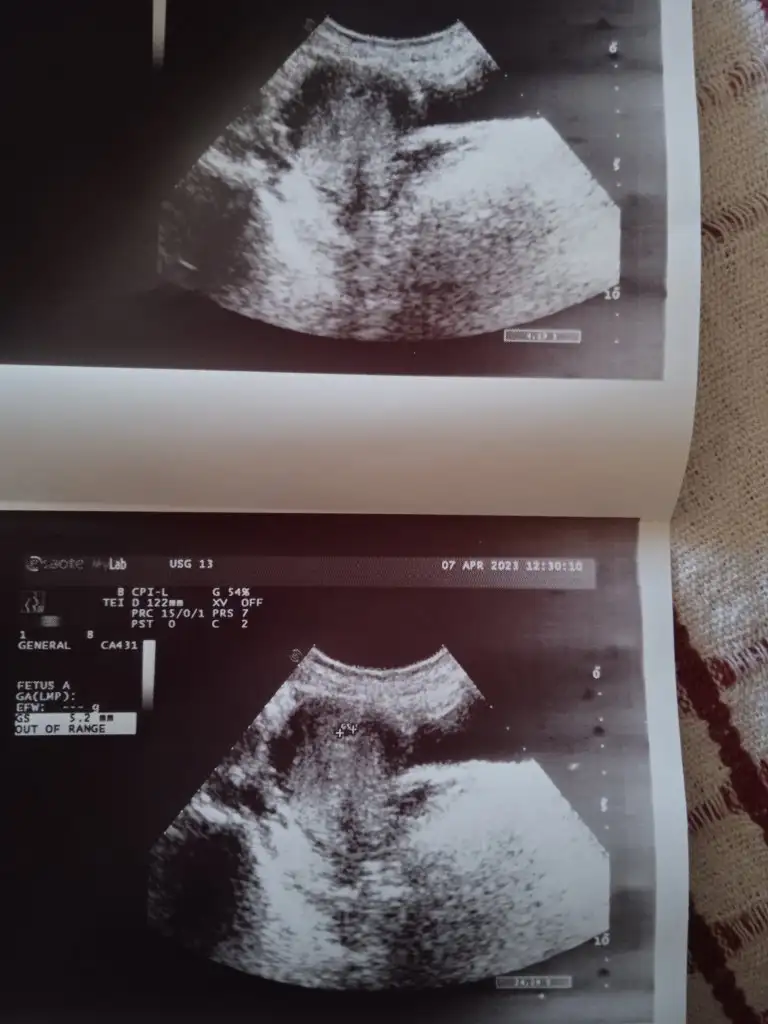

Canim benim geç döllenme olduğu için kaç haftalık olduğunu söylemedi doktor ona çok moralim bozuldu. Normal adet tarihime göre 7 haftalık çıkıyor ama geç döllenme işteMasallah Allah sağlıkla kucağınıza alabilmeyi nasip etsin kac günlükte gorundu kese bende 4+6 da gidicem de doktora acaba kese görünür mu

Merhaba geç döllenmede beta kalça öğrendiniz nasıl ilerledi sanırım benim de geç döllenme o yüzden soruyorumCanim benim geç döllenme olduğu için kaç haftalık olduğunu söylemedi doktor ona çok moralim bozuldu. Normal adet tarihime göre 7 haftalık çıkıyor ama geç döllenme işte

Selam Canım, benim 1 Mart yumurtlama günümdü, 15 Mart'ta adet olmam gerekiyordu olmadım, 1 hafta sonra yani ayın 22sinde kan verdim negatif çıktı. 1 hafta daha bekledim, bu arada tarih 30 Mart oldu ve gecikmemin üstünden 15 gün geçmişti bir daha kadın doğumda kan testi verdim ve 209la pozitif olduğunu öğrendim.Merhaba geç döllenmede beta kalça öğrendiniz nasıl ilerledi sanırım benim de geç döllenme o yüzden soruyorum